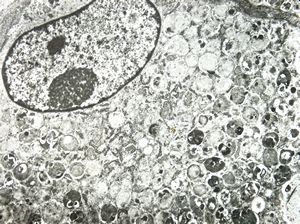

normal seromucinous salivary gland